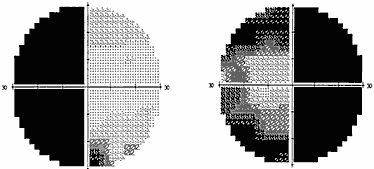

Общий анализ мочи. Дата проведения: 16.05.2003 уд. вес: 1017 Цвет: соломенно-желтый Прозрачность: прозрачная Реакция: кислая Белок: нет Сахар: нет Эпителий: 1-2 в поле зрения Лейкоциты: 0-1 в поле зрения ЭКГ от 17.05.2003 Горизонтальное положение электрической оси сердца, ритм синусовый, патологических признаков не обнаружено. Анализ крови на RW от 17.05.2003 - отрицательный. Заключение окулиста от 3.05.2003 Частичная нисходящая атрофия зрительных нервов, частичная битемпоральная гемианопсия, ангиопатия сетчатки. Гистологическое исследование от 22.05.2003 Гистологический препарат представлен 3 узлами от 0,7 до 2 см, дрябловатой консистенции, желто-белового цвета Заключение: Аденома гипофиза. Топический диагноз: Битемпоральное снижение зрения связано с поражением медиальных отделов хиазмы; кроме этого в патогенезе заболевания – увеличение размеров турецкого седла, аносмия при операции. Предварительный диагноз: Аденома гипофиза. Дифференциальная диагностика: Необходимо дифференцировать аденому гипофизу со следующими заболеваниями: 1) Рассеяный склероз; 2) Опухоль задней доли головного мозга. 1. Заболевание рассеянный склероз встречается в основном в молодом возрасте (21-25 лет), и имеет в первые годы развития ремитирующее течение (клиника исчезает бесследно без лечения), далее с каждой новой атакой клиника нарастает с периодическими ремиссиями. Этим он отличается от клиника развития заболевания нашего больного – аденома гипофиза обычно впервые проявляется в старшем возрасте, реже – в детском; патология проявилась два года назад, постоянно прогрессировала без возникновения ремиссий. Кроме этого, клиника рассеянного склероза характеризуется множественными поражениями: пирамидных проводников, мозжечка, мозжечковых ножек, миелиновых оболочек II, VI, VII пар черепно-мозговых нервов. При аденоме гипофиза поражается в основном область турецкого седла; при разрушении диафрагмы турецкого седла может врастать в полость черепа; при росте вверх - оказывает давление на хиазму и гипоталамус, в сторону – на зрительный тракт (что имеет место у нашего пациента), назад – разрушение стенки турецкого седла и опущение опухоли по скату черепа. При рассеянном склерозе имеет место зрительные нарушения по типу атоксии, как и при аденоме гипофиза. Но при рассеянном склерозе, обычно происходит сочетание нарушений: патология зрения по типу ретробульбарного неврита (снижение зрения, которое затем восстанавливается), как выше сказано – атоксии как мозжечковые нарушения, патология пирамидных проводников (центральные парезы конечностей); кроме этого – может быть двоение в глазах, косоглазие, парез лицевого нерва. Данных изменений у нашего больного не отмечено. 2. Опухоль задней доли головного мозга характеризуется как и аденома гипофиза наличием тех же общемозговых симптомов: головная боль, тошнота, рвота, изменения мозгового вещества на КТ. Но отличием для опухоли задней доли головного мозга является то, что головная боль имеет нарастающий характер и связана с повышением внутричерепного давления, чаще это ночные, предутренние или утренние боли – у нашего больного головная боль имела постоянный характер и не была связана со временем; тошнота и рвота возникают на высоте головной боли - у нашего больного тошнота и рвота не связаны с появлением головных болей; на компьютерной томографии головного мозга отмечается изменение мозгового вещества особенное вокруг желудочков, что свидетельствует об отёке – у нашего больного на КТ отмечается небольшое круглое образование в районе турецкого седла. Как и при аденоме гипофиза для опухоли задней доли головного мозга характерно наличие дефектов зрения, которые выражаются в коллатеральной гемианопсии, зрительных галлюцинациях, оптической и предметной агнозии, метаморфопсии – но при аденоме гипофиза у нашего больного отмечается лишь битемпоральная гемианопия, которая выражается в уменьшении боковых полей зрения. На основании вышеперечисленных фактов можно исключить у нашего больного диагнозы рассеянного склероза и опухоли задней доли головного мозга. Основываясь на вышеперечисленных данных можно поставить окончательный клинический диагноз. Клинический диагноз : Аденома гипофиза. Теоретическая часть. Среди всех опухолей, поражающих гипофиз, аденома занимает первое место. Обычно аденома гипофиза встречается у взрослых, но иногда опухоль обнаруживается и в детском возрасте. Аденома гипофиза – доброкачественная опухоль, развивающаяся из передней доли гипофиза. В настоящее время опухоли классифицируются, как секретирующие и несекретирующие. -Клинические проявления аденомы гипофиза Клиническая манифестация аденомы гипофиза разнообразна и зависит, во–первых, от типа опухоли (секретирующая, несекретирующая); во–вторых, от окружающих опухоль структур и степени их сдавления. Опухоль небольших размеров (микроаденома – до 10 мм в диаметре), локализующаяся в пределах турецкого седла, проявляет себя эндокринными расстройствами. В силу характера клинических проявлений (нарушение менструального цикла, снижение потенции, развитие акромегалии) нередко аденому гипофиза выявляют на этом этапе развития заболевания. Однако если опухоль относится к несекретирующим или пациент не придает достаточного значения имеющимся у него эндокринным нарушениям, если аденома развивается у пациента в пожилом возрасте, то опухоль достигает размеров больших, чем размеры турецкого седла и по мере роста распространяется за его пределы. На этом этапе развития процесса и появляется, как правило, офтальмологическая симптоматика. Таким образом, от офтальмолога во многом зависит диагностика процесса, а следовательно, и своевременное лечение пациента. Вот почему так важно знать офтальмологические проявления заболевания. Офтальмологическая симптоматика обусловлена локализацией и направлением преимущественного роста опухоли (О.Н. Соколова, 1959). Аденома гипофиза может распространяться в различных направлениях. Чаще опухоль, увеличиваясь в размере, распространяется за пределы турецкого седла через естественное отверстие в диафрагме седла и растет вверх по направлению к зрительному пути на основании мозга; к хиазме и интракраниальному отрезку зрительных нервов – интра–супраселлярный рост. Супраселлярный рост опухоли приводит, как правило, к развитию хиазмального синдрома. Хиазмальный синдром включает в себя битемпоральные дефекты поля зрения (рис. 1) и побледнение дисков зрительных нервов по типу первичной нисходящей атрофии.

Рис. 1. Полная битемпоральная гемианопсия (автоматическая статическая периметрия) При наиболее часто встречающемся срединном варианте расположения хиазмы опухоль начинает сдавливать центральные перекрещенные волокна нижней поверхности хиазмы, идущие от носовых половин сетчатки. Клинически это проявляется появлением дефектов в верхних височных квадрантах поля зрения на обоих глазах – начальный хиазмальный синдром. Следует отметить, что дефекты в поле зрения поначалу можно выявить только с помощью цветных объектов, красного и зеленого. Исследование поля зрения на цвета более чувствительно, чем кинетическая периметрия на белый цвет. Острота зрения на этом этапе развития заболевания, как правило, сохраняется нормальной. Диски зрительных нервов обычной окраски. Постепенно, по мере роста опухоли, усугубляются битемпоральные дефекты поля зрения, начальный хиазмальный синдром переходит в развернутый хиазмальный синдром с полным или почти полным выпадением височных половин поля зрения. Появляется побледнение дисков зрительных нервов преимущественно в височной половине – развивается первичная нисходящая атрофия зрительных нервов. Важно знать, что изменения на глазном дне наступают спустя месяцы от момента развития первых дефектов поля зрения. Нередко, к сожалению, пациенты не фиксируют внимания на периферических дефектах в поле зрения и обращаются к офтальмологу только тогда, когда появляется понижение остроты зрения. Справедливости ради следует сказать, что порой и врачи не придают должного значения жалобам пациентов в случае сохранной остроты зрения и/или нормального диска зрительного нерва. Пациенты годами наблюдаются и лечатся у офтальмологов по поводу атрофии зрительного нерва. Понижение остроты зрения имеет место при воздействии опухоли на интракраниальный отрезок зрительных нервов, когда в процесс вовлекается папилло–макулярный пучок. Это происходит либо при непосредственном сдавлении зрительного нерва опухолью, либо в результате смещения его опухолью и придавливания нерва к серповидной связке или костным структурам интракраниального отверстия зрительного канала. Клинически симптом воздействия на интракраниальный отрезок зрительного нерва проявляется центральной или парацентральной скотомой. Но чаще это сочетается с периферическими височными дефектами поля зрения. Понижение остроты зрения возможно и в результате распространения височного дефекта поля зрения на центральную зону. Понижение остроты зрения может быть на одном или на обоих глазах. Сочетание понижения остроты зрения на одном глазу или на обоих, но разной степени выраженности, и битемпоральных дефектов поля зрения приводит к развитию асимметричного хиазмального синдрома, свидетельствующего об асимметричном росте опухоли. Понижение остроты зрения, которое появляется прежде или в относительно короткий срок после развития битемпоральных дефектов поля зрения, указывает на преимущественный рост опухоли кпереди – супраселлярно–антеселлярно или о заднем расположении хиазмы. При таком расположении хиазмы опухоль локализуется перед хиазмой, воздействуя в первую очередь или преимущественно на интракраниальные отрезки зрительных нервов. Внимание пациента также могут привлекать парацентральные битемпоральные скотомы. Острота зрения при этом бывает высокой. Наличие таких дефектов поля зрения свидетельствует о сдавлении задне–верхних отделов хиазмы, вблизи расположения папилло–макулярного пучка. Подобная симптоматика имеет место при росте опухоли интраселлярно и преимущественно кзади – супраселлярно–ретрохиазмально или при переднем расположении хиазмы. Характерной первой жалобой пациентов при таком варианте роста опухоли может быть жалоба на затруднение при чтении. Следует, однако, оговорить, что такой тип зрительных расстройств при аденоме гипофиза встречается достаточно редко. В силу различных причин, в частности, из–за строения диафрагмы турецкого седла, опухоль может распространяться не столько кверху, сколько латерально, в сторону кавернозного синуса – латероселлярный рост. Зрительные нарушения, которые присутствуют при этом росте опухоли, чаще представлены асимметричным хиазмальным синдромом со значительным, вплоть до практической слепоты, понижением остроты зрения на одном глазу. Может также развиться одноименная (односторонняя) гомонимная гемианопсия (рис. 2) в результате воздействия опухоли на зрительный тракт. Дефекты поля зрения появляются в половине поля зрения на стороне, противоположной локализации опухоли. Офтальмологи должны быть внимательны, поскольку дефекты поля зрения при латероселлярном росте опухоли и развитии асимметричного хиазмального синдрома или гомонимной трактусной гемианопсии появляются в носовой половине поля зрения на глазу на стороне преимущественного роста опухоли (рис. 3). Это может спровоцировать ошибочную диагностику глаукомы.